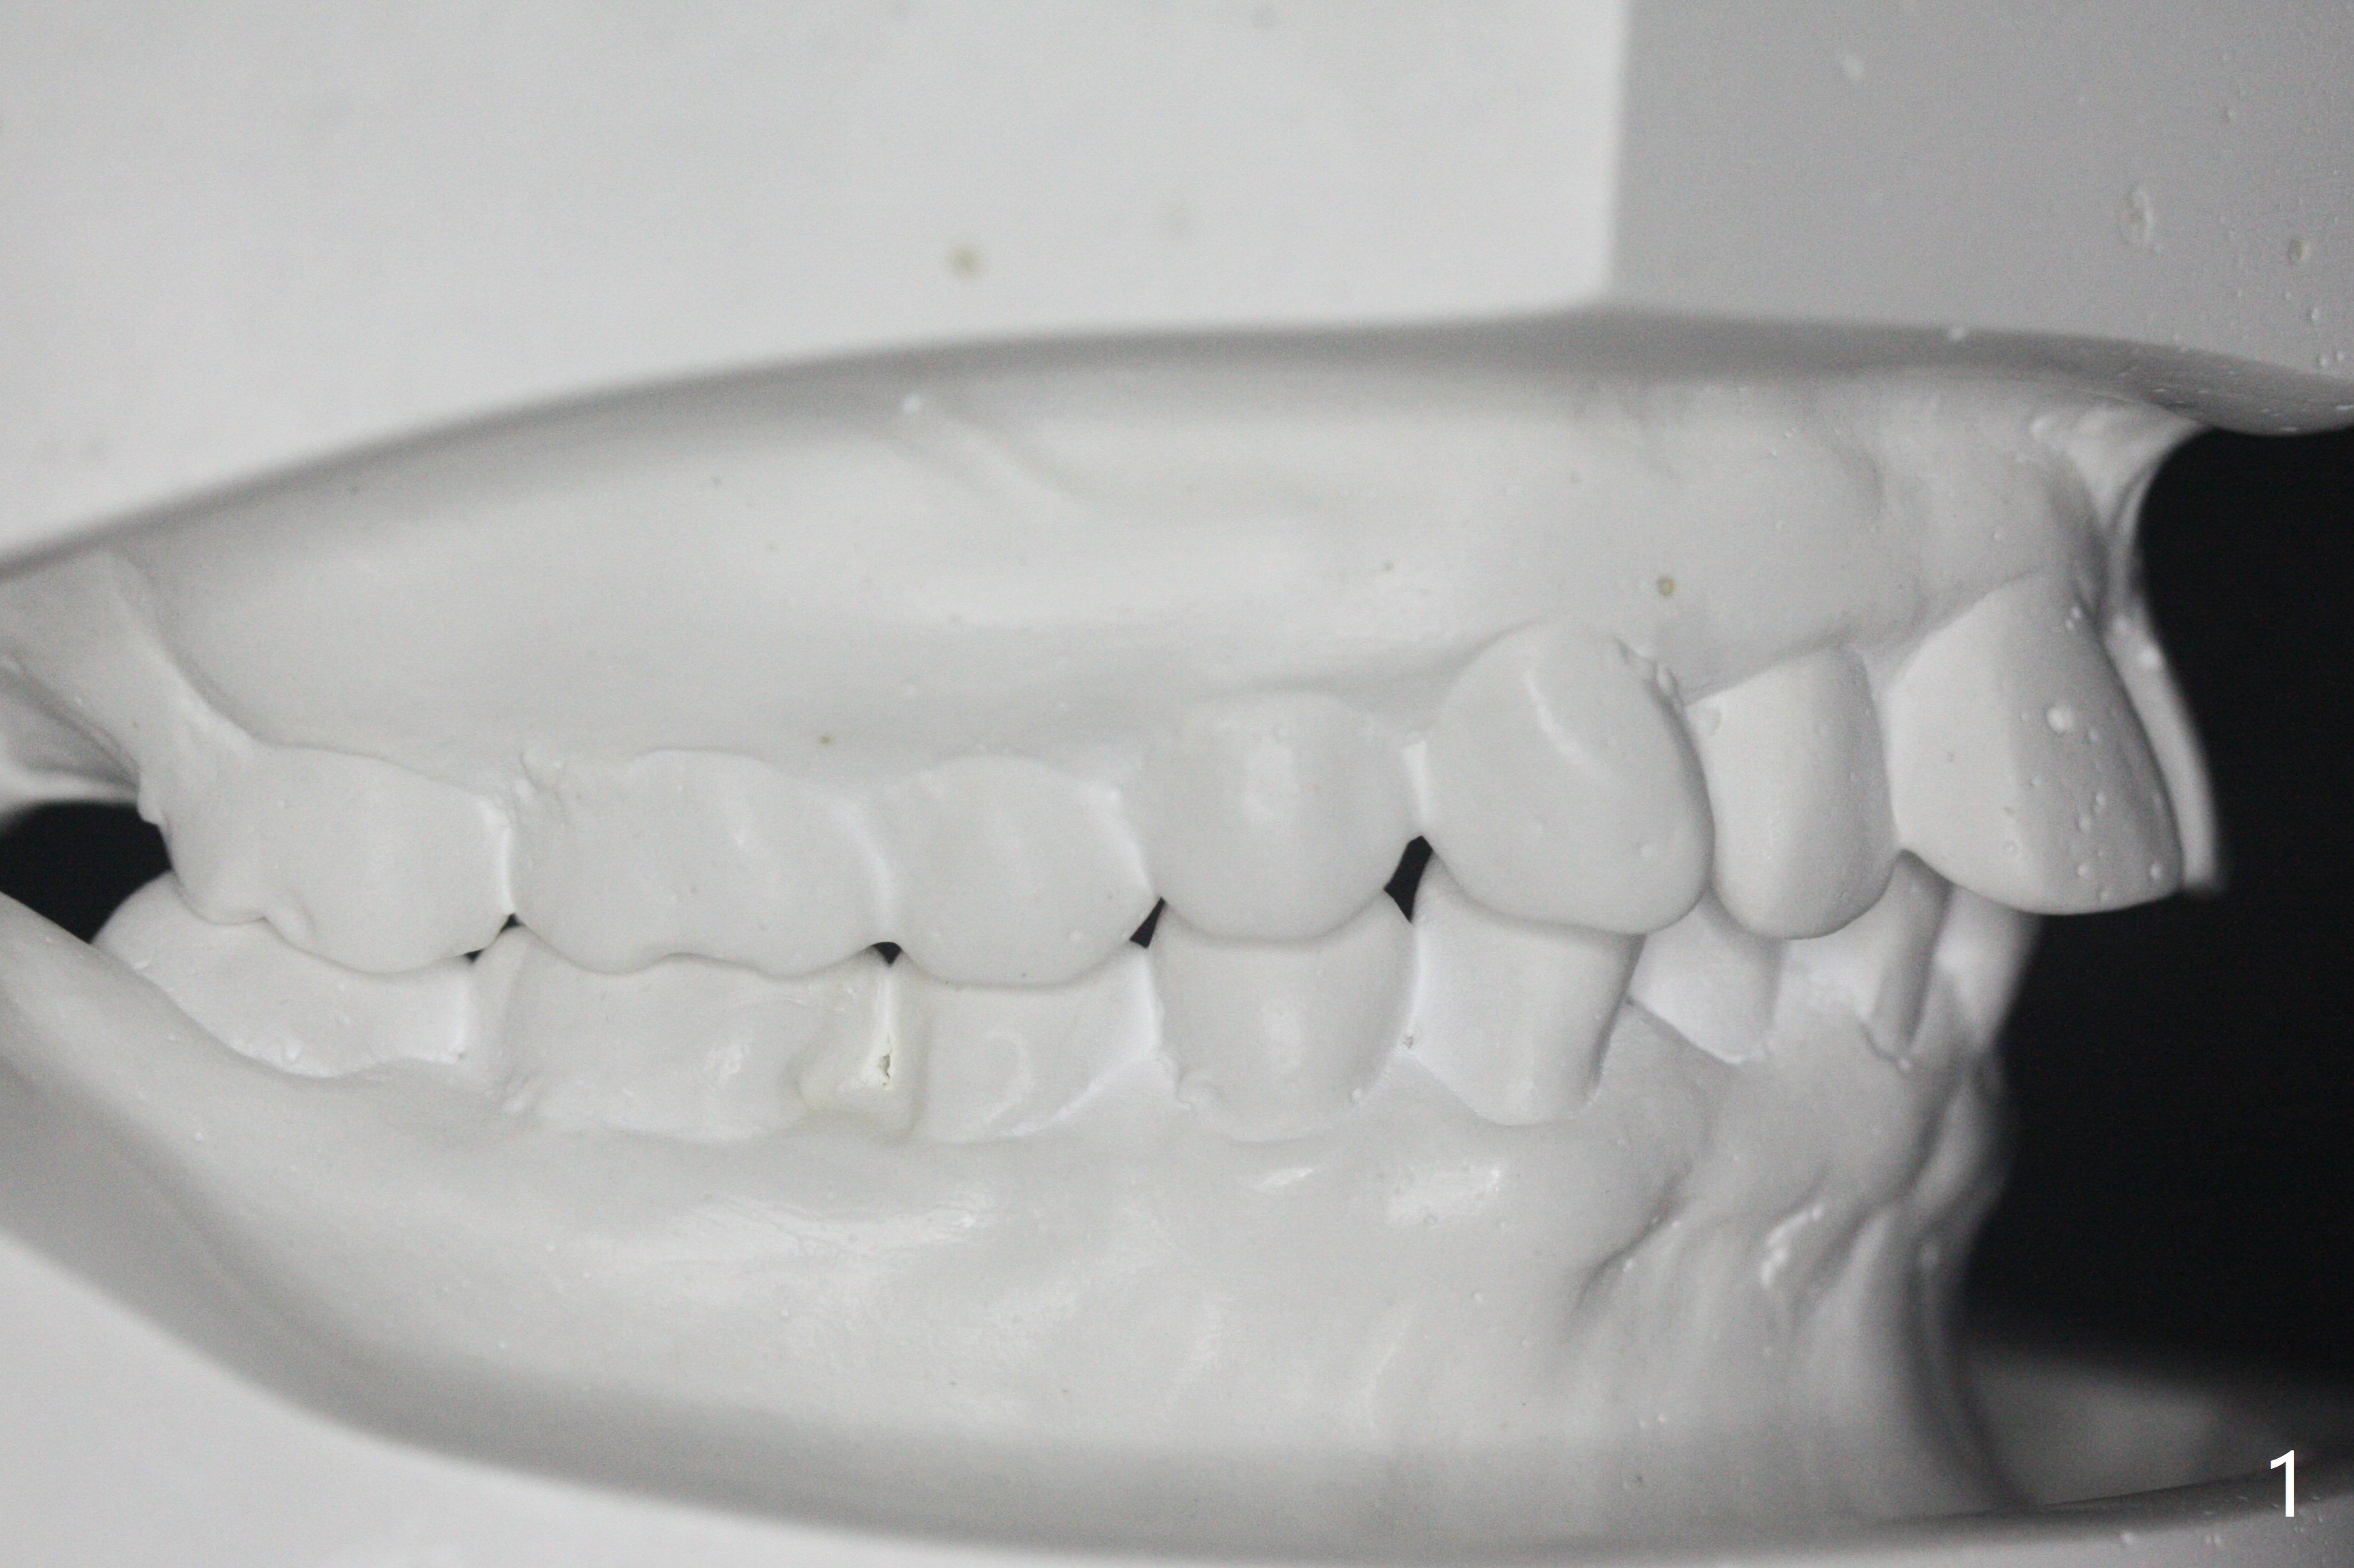

31岁女,牙周炎,安格氏二类错𬌗(图一至八),深洗后,同意牙齿矫正,但是要求保留左下智齿,前移7,8,取代6,左上6过度萌出(图三:箭头)。

初步计划:第一期安置矫正器,排列,建立正常前牙覆合覆盖,二类牵拉。尽量竖直左下7,8(图十一:白色轮廓);使用两个微型植体(图九:黑线(两个植体之间放置power chain(红线)))压入左上6(图十(圆圈:近中微型植体),与图三对比),为左下7近中移位(红色箭头)创造空间。

第二期在左下4和5之间植入微型植体作为支抗(图十一:红色),利用7远中长勾(粉红色)和橡皮筋,先让7平行近中移位,控制根torque。A 31-year-old woman with Class II Division I malocclusion requests orthodontic treatment without extraction of LL8. U8s and LL6 have been extracted with SRP. The 1st stage will be alignment , intrusion of UL6, upright of LL7 and 8 and correction of Class II malocclusion using double twin.